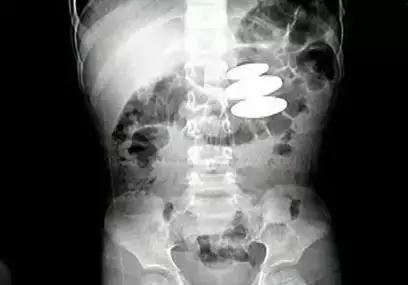

2、如果孩子吃了金属性异物(如硬币),要到医院做腹部透视,看看异物位于什么部位。如果异物大于5厘米,或形状特殊(如有角、刺),就很难通过食道或胃肠道,有可能嵌顿在胃肠道的某一部位,而不能从大便排出,必要时要考虑用胃镜或手术方法取出异物;

宝宝误吞异物,最好还是送医检查,最好带孩子到最近的医院拍一个正面和侧面的片子,让医生来判断异物在哪里,是不是要取出异物,这样也可以及时做好处理,让家长安心。